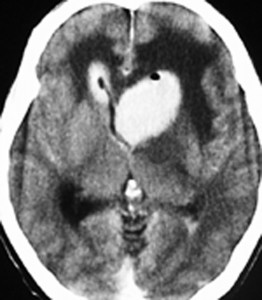

これは1990年代の古い例ですがリンパ腫の増大が早いことをお見せします。左側のはTHP-COPという化学療法をする前のものです。真ん中のは化学療法から4日目で,腫瘍は小さくなりました。でも,2コース目の化学療法の直前(4週間後)にもう一度MRIをしてみたらすごく大きくなっていました。この化学療法は効いているのだか効いていないのだか判らないことになります。化学療法を行なうならとても強い薬剤を使わなければなりませんし急がなければなりません。